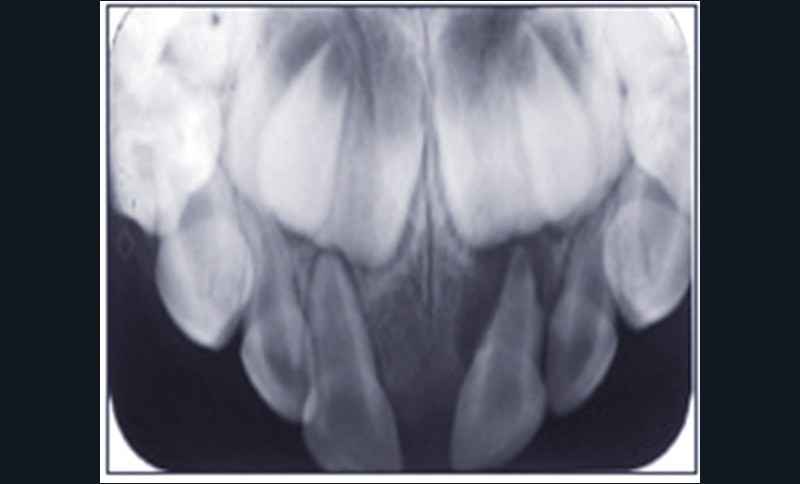

Les traumatismes des dents temporaires connaissent deux pics de fréquence entre 12 et 18 mois, et entre 3 et 4 ans. Ils interviennent donc souvent au cours de la croissance de l’appareil manducateur, avec de possibles conséquences sur le développement de celui-ci, et notamment sur les germes des dents définitives. C’est pourquoi le suivi des dents temporaires traumatisées jusqu’à la fin de la croissance est indispensable. Parmi les étapes qui doivent être surveillées, figure en premier lieu la formation de la dent définitive, qui sera surveillée radiographiquement. Son éruption peut également être perturbée par une dent temporaire traumatisée : le statut pulpaire de celle-ci sera surveillé cliniquement et radiographiquement. En effet, le risque infectieux subsiste après le traumatisme, et le suivi permettra d’éviter des cas de cellulites sévères. Si elle est nécessaire, l’extraction de la dent traumatisée pourra ainsi être réalisée au moment opportun. Enfin, dès la consultation qui a lieu après le traumatisme, les parents doivent être informés de l’importance du suivi, afin qu’ils y participent activement (fig. 1 et 2).

L’omnipraticien est très souvent confronté à cette question lors de sa pratique quotidienne : quel est le bon moment pour adresser les enfants chez l’orthodontiste ? La réponse peut recéler quelques difficultés, car elle est spécifique à chaque enfant. Le temps où il était conseillé d’attendre la denture définitive pour intervenir est révolu : certaines interventions précoces permettent aujourd’hui dans certains cas de raccourcir et de simplifier les traitements orthodontiques. C’est notamment le cas des anomalies transversales, qui sont celles qui sont traitées le plus précocement, dès 6 ans. Ainsi, lors d’anomalie cliniquement évidente, la consultation orthodontique s’impose. Cependant, certaines anomalies sont plus discrètes, et donc plus difficiles à dépister. Une panoramique doit toujours être réalisée en première intention afin de dépister les agénésies. Puis, même en l’absence d’anomalie évidente, il est recommandé d’adresser les enfants chez l’orthodontiste entre 7 et 9 ans : celui-ci sera ainsi à même d’adapter la prise en charge, et surtout l’âge idéal de prise en charge pour chaque patient(fig. 3 et 4).